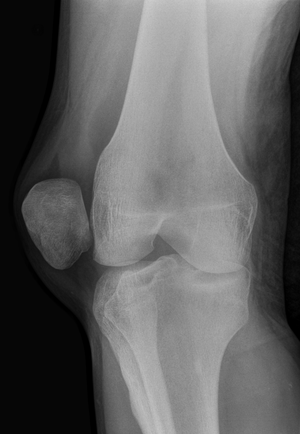

| Radiograph of a patient with patellar dislocation. Normally the patella projects over the distal femur. | |

Patellar dislocation is an injury of the knee, typically caused by a direct blow or a sudden twist of the leg.[1] It occurs when the patella (kneecap) slips out of its normal position in the patellofemoral groove, and generally causes intense pain with swelling of the knee.[1] Open or arthroscopic surgery may be used to repair damage, but are typically avoided since rates of re-injury, knee function, and patients' opinions do not differ much from conservative treatment.[2][3][4]

The patella generally dislocates laterally, and can be accompanied by acute pain and disability. Immediate reduction can be accomplished by hyperextension of the knee, and by providing a medialward pressure to move the patella back into the patellofemoral groove. Hyperextension of the knee on its own could possibly move the patella into place, because this motion locks the knee in place. When the knee is locked the ligaments are twisted and taut, allowing the muscles involved to relax and the patella to slide back into place.[5] If that does not work, a medical professional must manually perform an orthopedic reduction.[1] Swelling and impaired mobility follow patellar dislocation,[6] and a rehabilitation program of six to sixteen weeks is recommended whether or not the patient undergoes surgery.[3]